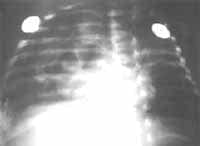

TAC de tórax

Se realiza TAC de tórax que reporta imágenes quísticas de paredes delgadas en lóbulo inferior derecho, atelectasia en lóbulo medio y língula (Figura 2). Se obtiene mejoría de cuadro de sepsis con estabilidad desde el punto de vista respiratorio, y es trasladada a piso para continuar su tratamiento.

| Figura 3. Biopsia de endometrio que muestra infiltrado linfocitario con presencia de granuloma no necrotizante constituido por células epiteloides, con células multinucleadas. | Figura 2. TAC de tórax en imágenes quísticas de paredes delgadas en lóbulo inferior derecho, atelectasia en lóbulo medio y ligula. |